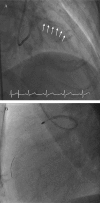

Figure 1.

Figure 1.. Heavily calcified left anterior descending artery (arrows) (A) with entrapped burr at middle to distal LAD (B).